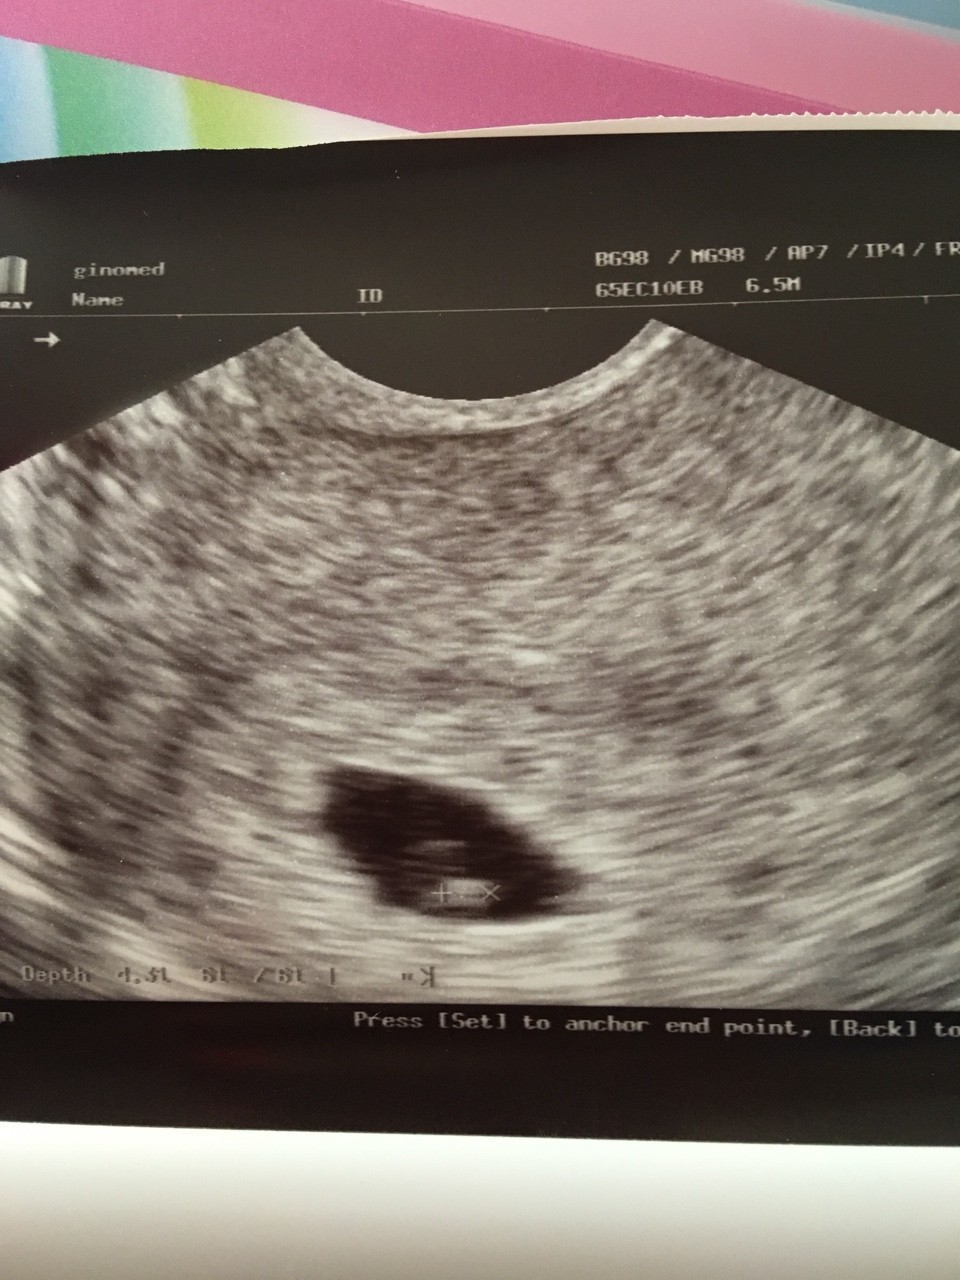

Tzn mialam na mysli ze akurat u mnie widac. A mialas regularne cykle?Na moim zdjęciu usg nie widacZobacz załącznik 866718